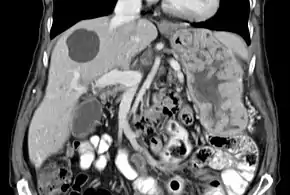

| Biopsy of the stomach in Ménétrier disease showing the substantial pit hyperplasia makes the large rugal folds appear to be covered by myriad polyps resembling hyperplastic polyps. The muscularis propria is the folded structure at the bottom center. | |

With Ménétrier disease, the stomach is characterized by large, tortuous gastric folds in the fundus and body, with the antrum generally spared, giving the mucosa a cobblestone or cerebriform (brain-like) appearance.[5] Histologically, the most characteristic feature is massive foveolar hyperplasia (hyperplasia of surface and glandular mucous cells).[3] The glands are elongated with a corkscrew-like appearance and cystic dilation is common. Inflammation is usually only modest, although some cases show marked intraepithelial lymphocytosis. Diffuse or patchy glandular atrophy, evident as hypoplasia of parietal and chief cells, is typical.[4]